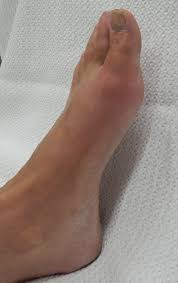

통풍은 주로 급격한 발작적인 증상을 보이며, 이는 주로 관절 부위에서 발생합니다. 통풍 발작의 주요 증상은 다음과 같습니다:

- 극심한 통증: 통풍 발작은 강한 통증을 동반합니다. 통증은 일반적으로 밤이나 새벽에 시작하여 관절 부위에 급격히 나타나며, 뚜렷한 통증을 유발합니다. 종종 "화살통 통증"이라고도 불리며, 통증의 강도는 매우 높을 수 있습니다.

- 부어오름과 발적: 통풍 발작 부위의 관절은 붓고 붉게 변할 수 있습니다. 특히 발가락의 발적이 흔하며, 관절 주위에 염증이 발생하는 결과입니다.

- 열감과 민감도: 통풍 발작으로 인해 발작 부위는 뜨거워지고 민감해질 수 있습니다. 심한 경우, 신체의 발열과 함께 민감도가 증가하는 것을 경험할 수 있습니다.

통풍 발작은 종종 몇 시간에서 몇 일 동안 지속될 수 있으며, 스스로 호전되기도 하지만 증상이 계속되거나 심해질 경우 의료 전문가와 상담하는 것이 중요합니다. 통풍은 치료 및 관리가 가능한 질환으로, 적절한 치료와 생활 습관 조절로 증상을 완화하고 재발을 예방할 수 있습니다.